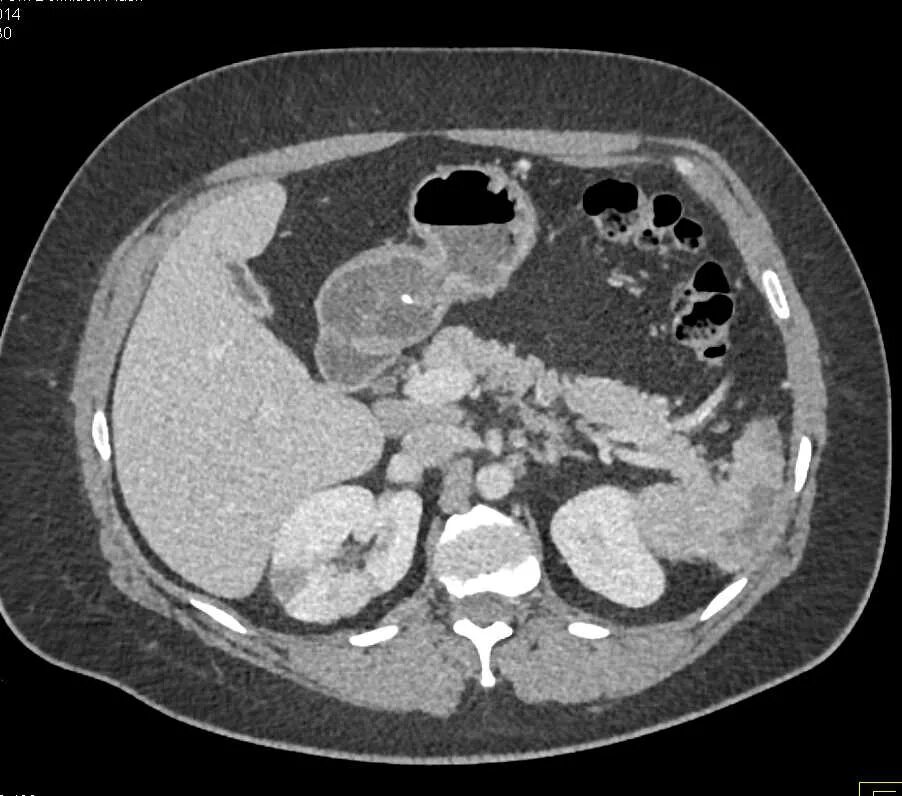

Пиелонефрит кт